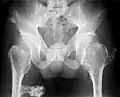

A noticeable lump in relation to an extremity may be the first presenting symptom. Multiple deformities can arise, namely coronal plane deformities around the knees, ankles, shoulders, elbows, and wrists. For example, genu valgum (knock knees), ankle valgus, ulnar bowing and shortening, and radial head subluxation are encountered. The majority of affected individuals have clinically manifest osteochondromas around the knee. Forearm involvement in HMO is considerable.[1][4] Furthermore, short stature may occur and is generally disproportionate. Such manifestations usually result from disruption of physeal growth especially that osteochondromas typically arise at the metaphyseal ends of long bones in close proximity to the physis.[1][4] Intra-articular osteochondromas of the hip can induce limitation of range of motion, joint pain and acetabular dysplasia.[2] Likewise joint pain at other locations and neurovascular compression can occur. Furthermore, functional disability in regard to activities of daily living can be a presenting feature. Spinal deformity pain or neurological compromise should arouse suspicion of involvement of the vertebrae.[3]

The diagnosis of HMO is based upon establishing an accurate correlation between the above-mentioned clinical features and the characteristic radiographic features. Family history can provide an important clue to the diagnosis. This is supplemented by testing for the two genes in which pathogenic variants are known to cause HMO namely EXT1 and EXT2. A combination of sequence analysis and deletion analysis of the entire coding regions of both EXT1 and EXT2 detects pathogenic variants in 70–95% of affected individuals.[3][4] The hallmark of radiographic diagnosis is the presence of osteochondromas at the metaphyseal ends of long bones in which the cortex and medulla of the osteochondroma represent a continuous extension of the host bone. This is readily demonstrable in radiographs of the knees.[3][1]